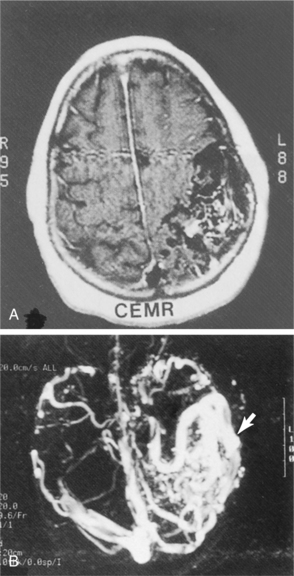

The availability of CT allows for prompt diagnosis of ICH. The specific area of damage can be imaged and the amount of blood identified. CT also has documented acute clot retraction progression of hyper tensive ICH and early hemorrhagic infarction. It accurately documents the size and location of the hematoma, the presence and extent of any mass effect, and the presence of hydrocephalus and intraventricular hemorrhage. CT scans should be performed immediately in individuals suspected of having an ICH. Follow-up CT scans are requested when there is a change in clinical signs or state of alertness in order to monitor changes in the size of the lesion and ventricular system and to detect important pressure shifts. If the clinical syndrome and CT findings are typical of hypertensive hemorrhage in the basal ganglia, caudate nucleus, thalamus, pons, or cerebellum, angiography is usually not necessary. If the hemorrhage is in an atypical location, the individual is young and not hypertensive, angiography is indicated to exclude an AVM, aneurysm, vasculitis, or tumor. Individuals who have ICH after cocaine use have a high likelihood of vascular malformations and aneurysms and need angiography. Particular attention should be directed to the presence of a coagulopathy. A drug screen should be obtained to evaluate use of sympathomimetics if substance abuse is suspected. Increased sympathetic outflow due to the hemorrhage may lead to an increase in dysrhythmias. Dysrhythmias also may signal impending brainstem compression from an expanding hemorrhage.

MRI can provide multiplanar views and can discriminate subtle tissue changes and rapidly flowing blood. However, it is of limited usefulness in the first 24 hours after ICH. MRI has the capability to detect previous hemorrhage, and it can image the posterior fossa more clearly than can CT.